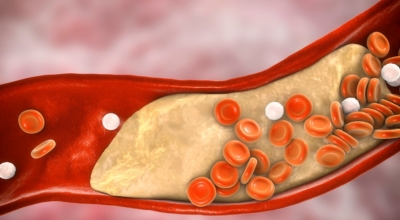

호두, 아몬드등의 견과류 섭취는 필수지방산이 많이 포함되어있다고 하며 콜레스테롤을 낮춰주어 고혈압 감소시키는 음식입니다. 등푸른 생선에 많이 들어있는 불포화 지방산은 혈관벽에 붙어서 혈관을 좁게 하는 포화지방을 없애주는 효과가 있어 고혈압에 좋으니 필수로 챙겨드시기 바래요.